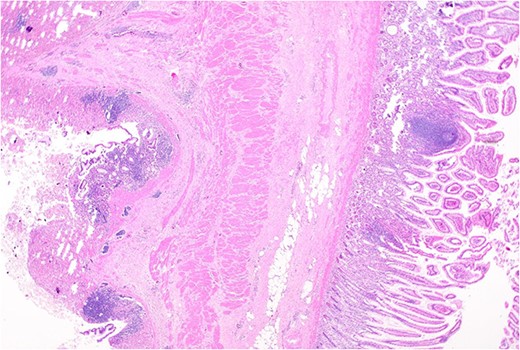

Histopathology macroscopically identified a 42-mm cystic caecal mass adjacent to the ileocaecal valve (Figs 4–5). Microscopic examination revealed a duplication cyst involving the ileal and colonic tissue comprised of a complete duplication of the colonic wall including mucosa, submucosa and muscularis propria, which was shared with the involved colon (Fig. 6). There was no mucosal connection to adjacent normal bowel. There was some ulceration with inflammatory changes in the overlying mucosa suggestive of prior cyst perforation and areas of attenuated villiform mucinous epithelium with features of low grade dysplasia (Figs 7-8). Special stains for organisms (Periodic Acid-Schiff (PAS), Fredericamycin A (FMA), Ziehl-Neelsen (ZN) and modified ZN) were negative. There were no granulomas, heterotopic mucosa or evidence of malignancy. Twenty-nine lymph nodes were identified with no evidence of malignancy.

Area of dysplastic mucosa (right) within the duplication cyst that shares a common wall with the right colon (left), low power.

Low grade dysplasia in duplication cyst epithelium, high power.